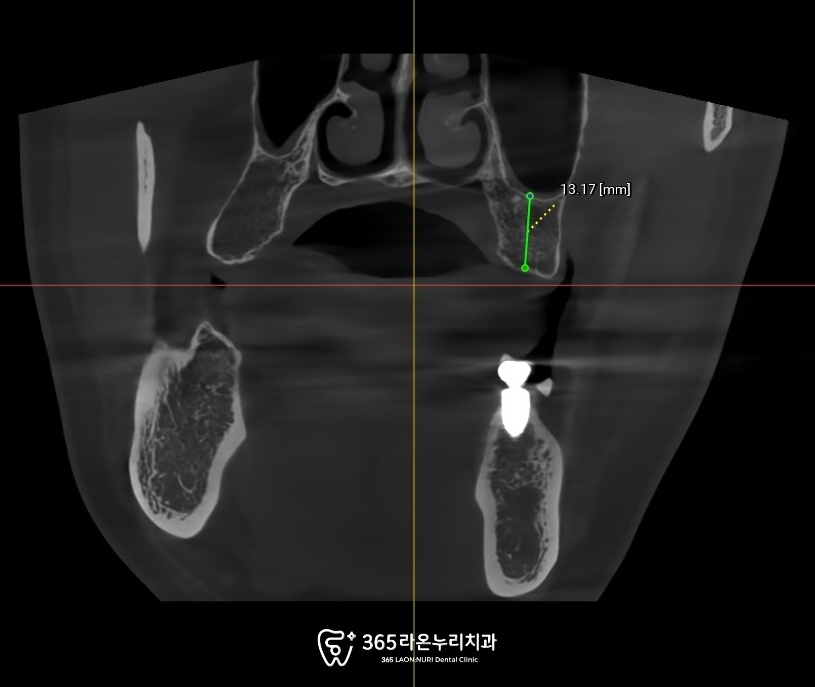

CT를 통해 더 이상

기능을 못하는 것을 확인하였습니다.

확실한 치료를 위해서는

큐레이 검사와 CT

검사를 동반해 주는데요.

이 과정을 통해

임플란트 식립을

먼저 진행해 주어야 됩니다.